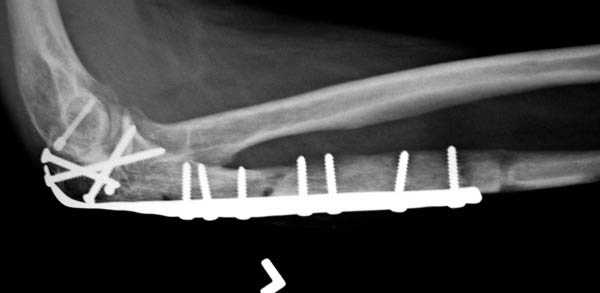

3 вариант

перелом с capitellum humerus и проксимальной трети улна